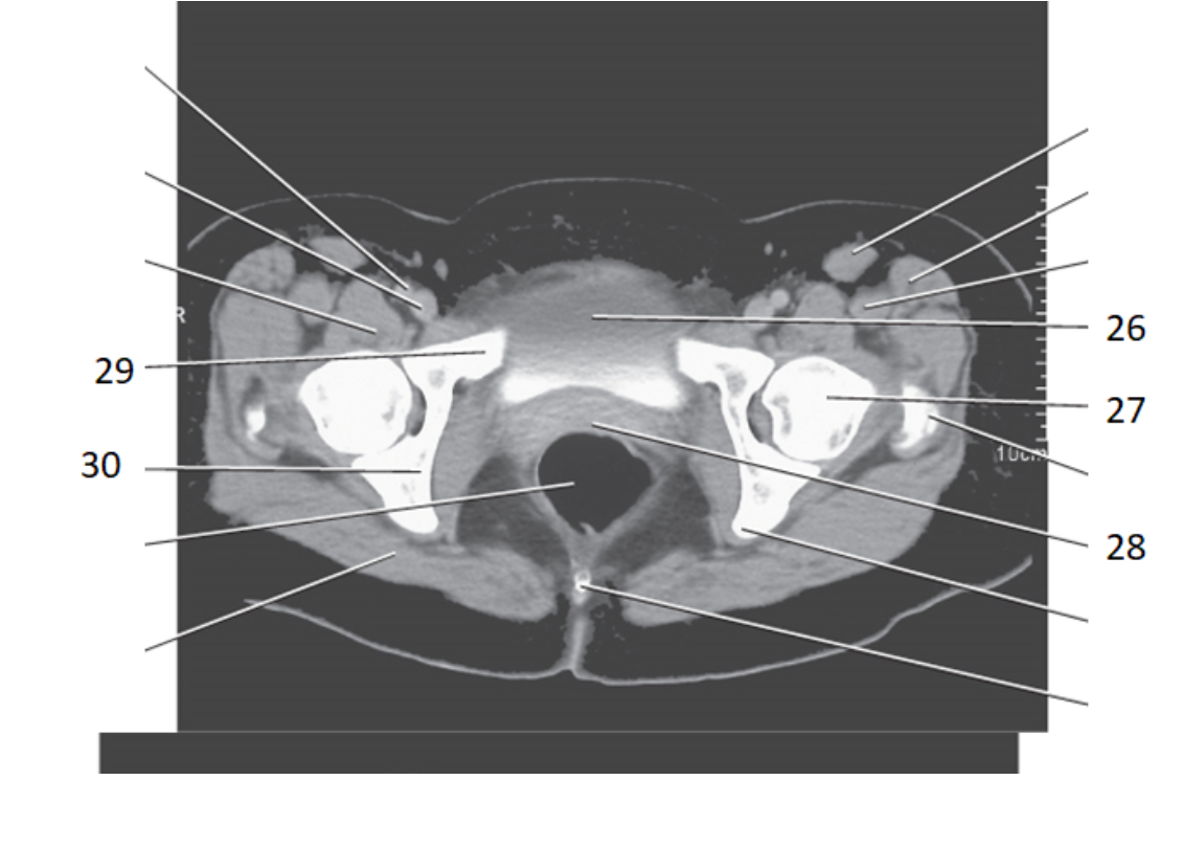

29

pubis

30

ishium

6

ilium

rectum

14

acetabulum

31

seminal vesicles

28

bladder

17

pubic symphysis